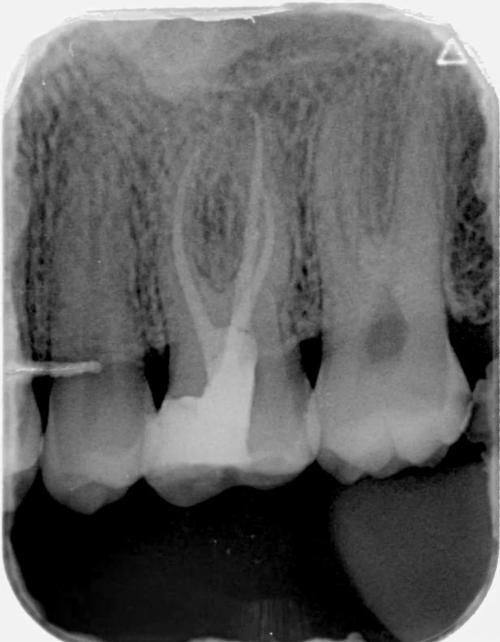

4. 牙体牙髓病治疗:配备牙髓测量仪、热牙胶充填设备等精良器械,开展根管治疗、补牙等项目,精细处理牙髓炎、根尖周炎等问题,保留天然牙功能。